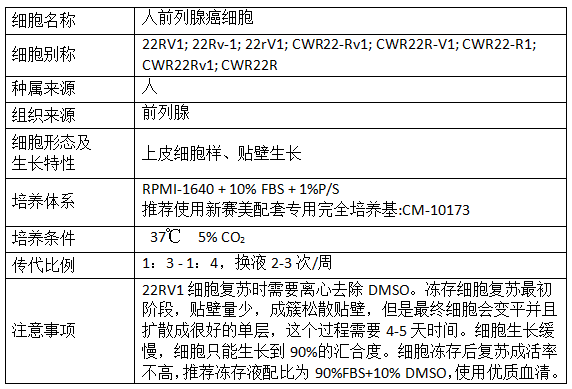

产品信息: